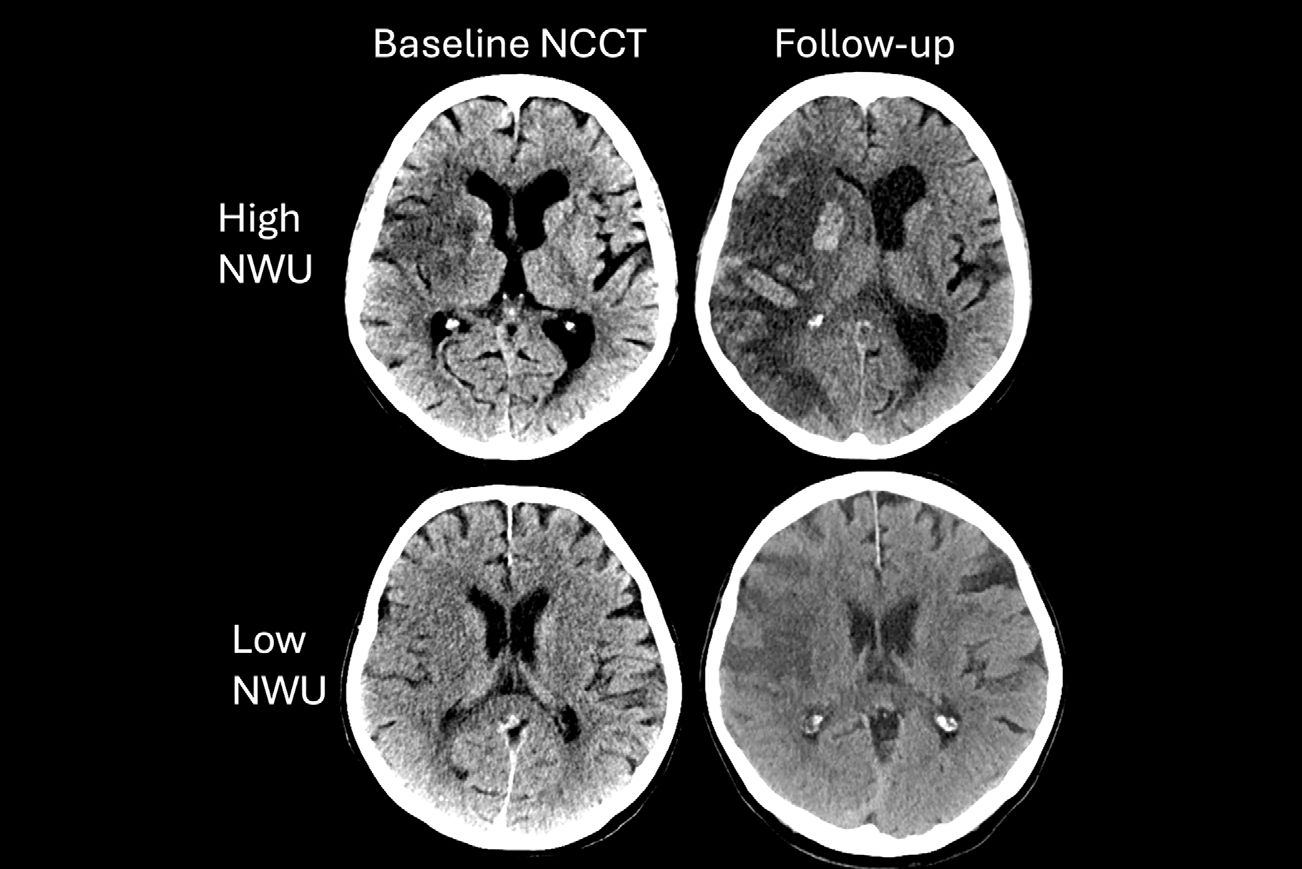

Wolansky is well-known for his neuroimaging research in multiple sclerosis, brain tumors, and MRI contrast agents; he recently published a study on the use of computer-assisted diagnosis to improve diagnostic accuracy and efficiency, according to the University of Connecticut.